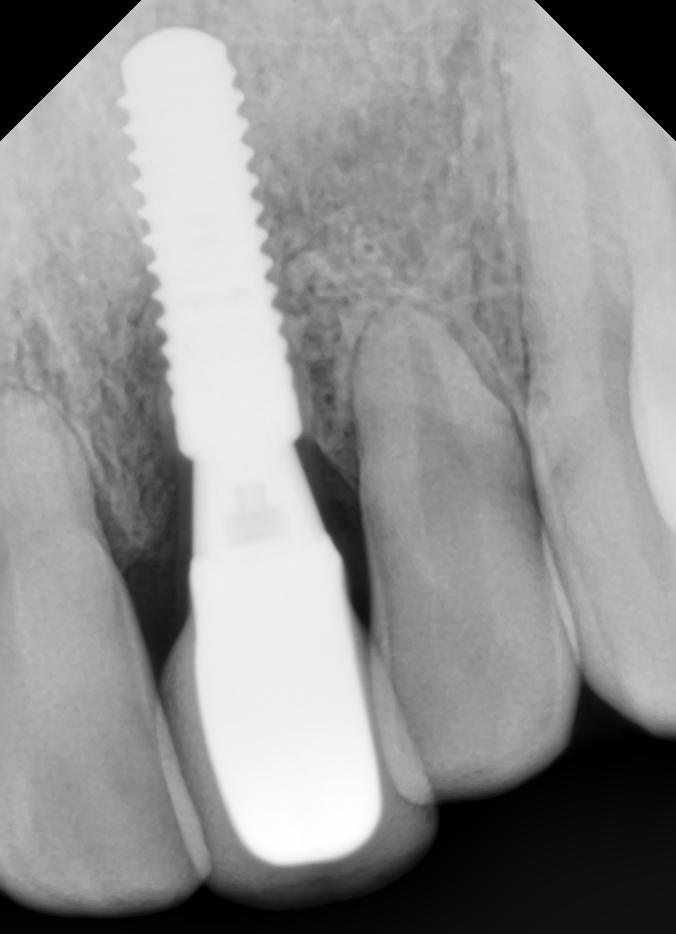

Nejelegantnější a také nejplnohodnotnější náhradou zubů jsou však zubní implantáty. Zubní implantát je miniaturní šroubek. Tento umělý kořen tvoří stabilní základ pro dlouhodobé upevnění korunky; broušení sousedních zubů odpadá, ztráta kostní masy na základě onemocnění parodontu a atrofie kosti (úbytek v důsledku nezatěžování kosti v místě chybějícího zubu) je vyloučena, neboť implantáty přenášejí žvýkací síly do kosti a podněcují tak její regeneraci. Implantát jako náhrada kořene zubu je nejlepší způsob, jak docílit vyplnění mezery po chybějícím zubu. Zubní implantáty jsou také jisté ukotvení pro snímatelné protézy a ušetří pacienty před známými nevýhodami konvenčního „umělého skusu“.

Pokud se rozhodnete pro implantáty Straumann švýcarské výroby, získáte tím jedinečné výhody léty prověřeného systému. Straumann zubní implantát je šroubovitý podpůrný pilíř, který nahrazuje přirozený kořen zubu. Implantát je zaveden do čelisti, kde se průměrně asi po 3-4 týdnech (platí pro typ SLActive) usadí, respektive vhojí. V 80% případů je lze okamžitě zatížit speciální protetickou prací – pacient je bez zubů 3dny. Straumann zubní implantáty jsou vyráběny z čistého technického titanu třídy 4 či kombinace titanu a zirkonia. Tento materiál je bez komplikací přijímán lidským organizmem, alergické reakce se nevyskytují.